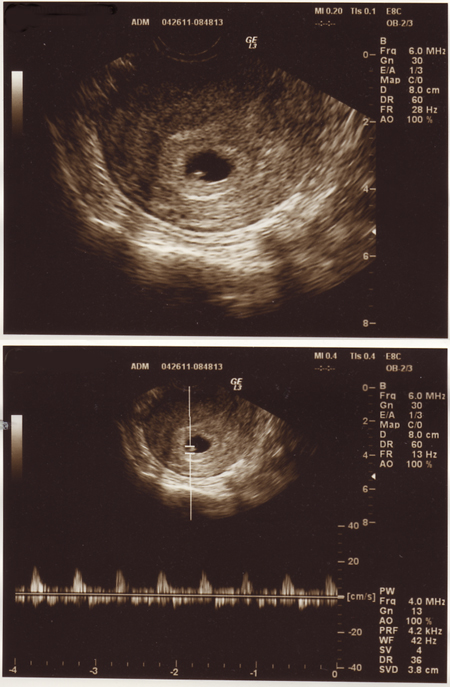

現在8週と4日。

ベビーさんは元気にしていました。

左側が頭。横向きかな。

背中丸めて、下向いてます。

よーく見ると、ちょろんと手足が出てるのがわかります。

ぽよんと浮いてる丸いのは、卵黄嚢(らんおうのう)という栄養で、赤ちゃんのお弁当。